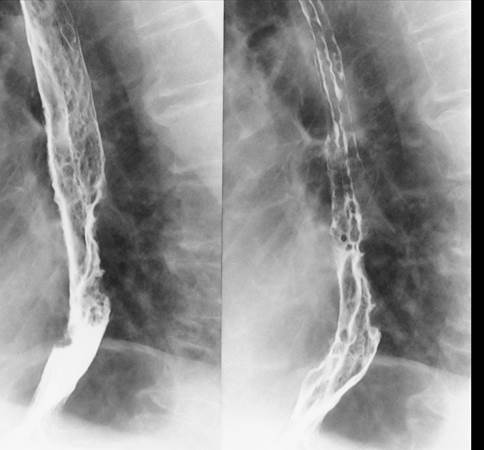

Спектральная компьютерная томография пищевода. Выявлена усиленная и дискоординированная перистальтика в средней и нижней трети пищевода, отмечено диффузное утолщение стенки средней трети до 7 мм на протяжении 6 см (рис.3).

Рис.3. Гастроптоз со спадением, деформацией и циркулярным сужением нижней трети пищевода при выявленной онкологии (КТ-гастро-томографии пациента с контрастным усилением висмутом бария).

Примечание: из личного архива авторов

Учитывая полученные данные неврологического статуса, лабораторных и инструментальных исследований, был поставлен вопрос о происхождении дисфагии у пациента П. С одной стороны, развитие дисфагии могло быть связано с невропатией черепных нервов вирусного генеза (с учетом лабораторных данных), но, принимая во внимание, что пациент болеет на протяжении двух лет и основной его жалобой было постепенное снижение массы тела и нарушение глотания жидкой и твердой пищи, было принято решение, что дисфагия может иметь смешанный генез, в том числе и пищеводный, и возникла вследствие сужения нижней трети пищевода, что приводило к нарушению прохождения пищи в желудок. Было проведено ПЭТ-МРТ пищевода и желудочно-кишечного тракта, которое выявило очаг новообразования пищевода, иммуногистохимическое исследование биопсийного материала верифицировало его как лейомиосаркому пищевода (T1N0M0).